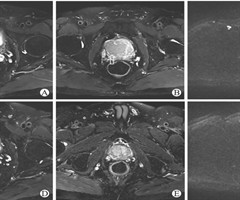

肾上腺出血3例报告并文献复习

中图分类号:R586.2 文献标志码:B DOI:10.3969/j.issn.1009-8291.2025.06.017 在急诊病例中,成人肾上腺出血罕见且病因复杂,缺乏特征性临床表现,处置及随访缺乏临床指南及标准化流程,易漏诊、误诊。上...